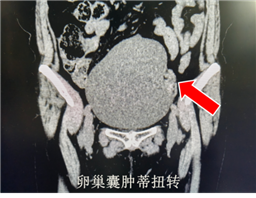

女性急腹症的诊断难点,向来在于“同症异病”的复杂局面。以CT室接诊患者为例,患者因腹痛就诊,既往具有阑尾炎病史,很容易先入为主怀疑阑尾炎复发,通过盆腔CT检查亦见阑尾增粗,管腔内见高密度粪石,然而值班医师敏锐捕捉到右侧附件区高低混杂密度这一关键特征,通过CT值测量,高度怀疑有出血,由此怀疑出发,经过仔细问询患者月经史,综合CT影像表现,最终诊断为卵巢黄体囊肿破裂。这一案例并非个例,本科室日间接诊另一病例中,同为女性腹痛来诊,CT检查可见盆腔巨大囊性肿物,经过CT室医师细致阅片后,结合解剖位置、形态特征及临床症状,诊断为卵巢囊肿蒂扭转,该患者于当日在我院手术证实该诊断正确。

影像学检查能通过清晰的图像,直观呈现腹腔内组织结构的细微变化,为疾病检备提供客观、精确的依据。CT检查在密度分辨力上占据优势,能够精准识别高低混杂密度、积液、炎性渗出等细节,尤其区分腹腔内出血、感染及实性病变时为最终确诊提供强有力的支撑,从而为临床治疗提供最可靠的决策依据,避免误诊给患者带来的不必要痛苦与治疗风险,精准破局,守护每一位患者的生命健康。